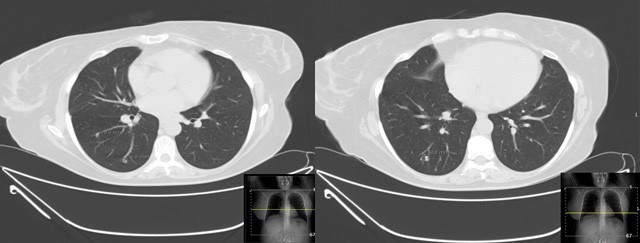

We present a case of a 47-year-old non-smoker, non- drinking Caucasian woman recently diagnosed with invasive squamous cell carcinoma of the tongue (cT2N0Mx). A decision was made to perform right hemiglossectomy with tumor exeresis and radical cervical lymphadenectomy. CT scan of the head, neck and chest were also performed for cancer staging. High resolution CT scan revealed three round subpleural nodules of uncertain etiology, located posterior and inferiorly in the right upper lobe and superiorly in the right lower lobe, measuring 6.8, 8.6 and 9 mm, the latter presenting cavitation. (Figure 1). No hilar or mediastinic lymphadenopathies were observed, and there were no pleural or pericardial effusions. No other remarkable changes were seen in the mediastinum or the lungs. The patient remained asymptomatic. CT guided transthoracic biopsy was required for nodule characterization, and biopsy of the 9 mm cavitary lung nodule (Figure 2) revealed pulmonary parenchyma with mostly preserved alveolar structure, partially occupied by spindle cell proliferation, without pleomorphism, necrotic areas, atypia or mitotic figures.

Immunohistochemical staining showed positivity for smooth-muscle actin, desmin and estrogen and progesterone receptors, while showing negativity for TTF1, AE1/AE3, bcl2 and CD34. The histological findings were compatible with BML (Figure 3). Due to these findings, the patient (who had no clinical history of known leiomyomas or other gynecological conditions) was referred to gynecological consultation and transvaginal ultrasound examination revealed a heterogeneous uterine wall with two intramural hypoechoic lesions (measuring 12 x 12 mm and 10 x 6 mm) and one subserosal hypoechoic lesion (measuring 54 x 28 mm), suggestive of uterine leiomyomas (Figure 4). The patient underwent hysterectomy and bilateral adnexectomy, and surgical histopathological study confirmed the diagnosis of multiple uterine leiomyomas, confirming the origin of the BML lesions found in the lungs. The latest postoperative CT chest scan for lung nodules evaluation showed overlapping characteristics, compared to previous imaging studies. As such, these BML lesions remain morphologically and numerically stable. The patient remained asymptomatic and was followed- up in consultation. No surgical or hormonal therapy was performed in regard to BML, and a CT chest scan was scheduled 6 months later to monitor the lesions.

Imaging features of BML are non-specific.2 Lung involvement in BML may appear as lung nodules on chest radiography or CT, ranging from solitary sub-centimetric lesions to multiple lesions similar to malignant metastases.2,8 The usual presentation is the presence of bilateral, well-circumscribed, non-calcified nodules diagnosed incidentally.2,3 Cavitation of these lesions may occur,2,3 as in our clinical case. More rarely, pneumothorax may take place, along with occasional cases of miliary pattern and pattern simulating interstitial disease.2 CT and MR imaging studies are often used to detect and describe these pulmonary nodules, which usually present homogeneous enhancement and non-specific appearance.2 As such, a list of differential diagnosis must be taken into account when considering possible BML lung nodules, including lung malignant metastases and, more rarely, infectious pulmonary granulomas, rheumatoid nodules, sarcoidosis and amyloidosis.2 In this clinical case, given the previous oncologic diagnosis and no known history of uterine leiomyomas, our main concern was to rule out malignant nature of these lung nodules, due to the possibility of distant metastases of oral squamous cell carcinoma.9,10 Imaging-guided biopsy is most often required to get a definitive diagnosis.